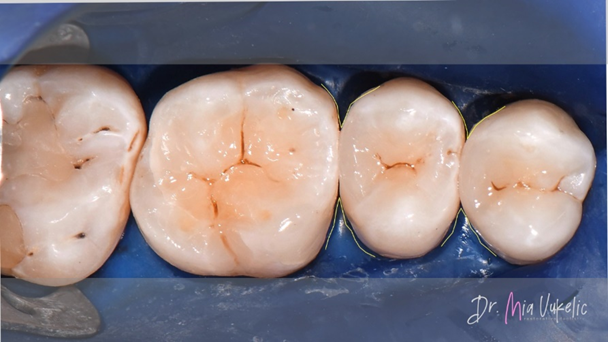

Dabei wurde eine modifizierte zentripetale Aufbautechnik eingesetzt. Im ersten Schritt wurde eine Schicht fließfähiges Komposit (Tetric EvoFlow™, Ivoclar*) mit einer Stärke von 0,5 mm aufgetragen.

Das Mittel der Wahl für die Restauration war Transcend™ Universalkomposit (Ultradent Products). Die Approximalwand wurde mit der Farbe EW erstellt. Für die beiden folgenden horizontalen Schichten wurde die Farbe A3D verwendet. Sekundärcharakteristika wurden mit dem Kolor + Plus™ Farbmodifikator – braun (Kerr*) erzielt.